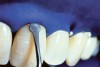

The whitening agents are available in various concentrations ranging from 10% carbamide peroxide (equal to 3.4% hydrogen peroxide) to 38% hydrogen peroxide. If the higher concentration agents contact the soft tissues, they can produce a chemical “burn” that turns the tissues temporarily white (Figure 1 and Figure 2). Although tissues quickly return to their normal color once they rehydrate, they may be mildly uncomfortable for a few hours. The patient may be distressed by the temporary appearance of the whitened soft tissues. A rubber dam or other protective barrier is mandatory to effectively seal off the tissues (Figure 3). In-office systems usually supply a light-cured resin in a syringe to apply around the cervical areas to confine the agent to the teeth (Figure 4 and Figure 5). In addition, flexible spreaders should be placed in the mouth to prevent the cheeks or lips from contacting the whitening agent.

Figure 3  Ideal rubber dam isolation should include inverting the material around the crown.

Figure 4  Manufacturer’s light-cured resin material syringed into the soft tissue to ensure proper isolation.

Figure 5  Manufacturer’s light-cured resin material syringed into the soft tissue to ensure proper isolation.